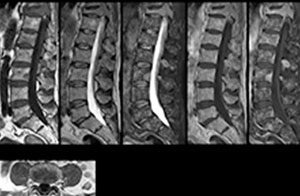

Including mDIXON TSE for robust fat suppression

“We use mDIXON TSE extensively in our spine imaging in the emergency room,” says Dr. Karis. “It’s particularly nice in that it is very robust with regard to susceptibility type of problems that would come up with traditional spectral fat-saturated images; these problems are essentially eliminated with the mDIXON technique. In our ED environment it’s really nice to have the fat-free imaging that goes along with the mDIXON technique.

“For the thoracic and cervical spine routine non-contrast exam, for example, we perform one mDIXON T2 TSE sequence, which provides us with two outputs: the fat-and-water-together T2-weighted images, as well as the water-only sagittal T2-weighted images. And then we also perform an axial gradient echo exam.”